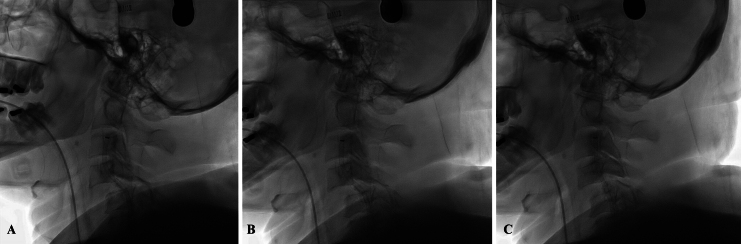

Background: Traumatic vertebral artery injury (TVAI) is a serious yet underdiagnosed complication of cervical spine trauma, with an incidence ranging from 0.1% to 3.2%. While its neurological sequelae vary, the risk of vertebrobasilar ischemia can be as high as 33.3%. The authors present a rare case of bilateral vertebral artery occlusion with concomitant basilar artery occlusion following C4-5 anterolisthesis.

Observations: The patient initially exhibited no clinical signs of vertebrobasilar ischemia. Diagnosis was achieved through vascular imaging, and successful endovascular thrombectomy with thrombus removal was performed. Unique to this case, manual cervical reduction was carried out in the endovascular suite while maintaining catheter placement in an effort to prevent recurrent dissection or emboli migration.